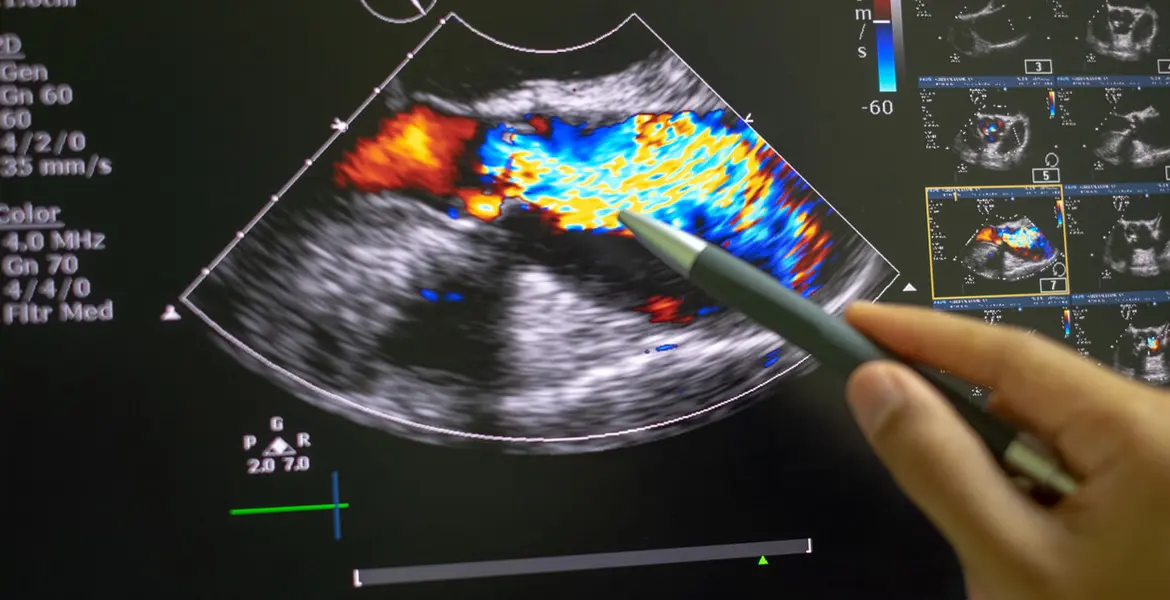

El ecocardiograma es un estudio con el que, mediante técnicas de ultrasonido, se puede ver en detalle la fuerza, forma, tamaño y movimiento del corazón.

Un ecocardiograma transesofágico es un estudio de imagen que, mediante ondas sonoras, crea imágenes del corazón y de sus estructuras.

En una ecocardiograma tradicional el transductor se coloca sobre el pecho, a diferencia del ecocardiograma transesofágico donde el transductor se inserta a través del esófago.

Al estar el esófago ubicado justo detrás del corazón, este ecocardiograma permite una visión mucho más cercana del corazón.

• Visualización detallada: las imágenes que ofrece del corazón y sus válvulas son de alta resolución lo que permite a los médicos identificar con mayor precisión cualquier tipo de anomalía estructural o funcional.